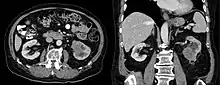

| Collecting duct carcinoma. H&E stain. | |